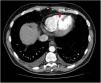

Caso clínicoSe trata de un varón de 56 años que acude a urgencia por disnea y malestar general. Como antecedentes destaca que es exfumador hace 9 meses y un bloqueo auriculoventricular de 1.° grado. El paciente refiere un episodio de dolor en epigastrio 5 días antes, cuando consulta a su médico y tras ser diagnosticado de epigastralgia es tratado con inhibidores de la bomba de protones. Durante los días siguientes persiste el mal estado general y palidez, y debido al empeoramiento clínico acude a urgencias de nuestro centro. El electrocardiograma muestra ondas Q en cara inferior, sin otras alteraciones a destacar y estando el paciente hipotenso (85/55mmHg) con mala perfusión distal. Leve movilización de troponinas cardíacas. Tras la clínica actual se solicita una tomografía computarizada (TC) pensando en posible tromboembolismo pulmonar que es descartado, sin ser informada de más hallazgos. Debido a la inestabilidad del paciente avisan al cardiólogo de guardia quién tras realizar una ecocardiografía transtorácica (ETT) observa lo que parece una comunicación interventricular a nivel ínfero-medial con importante shunt izquierda-derecha (fig. 1). Tras la revisión de la TC se objetiva un gran defecto el tabique interventricular en su porción medial (fig. 2). Confirmado el diagnóstico se decide no realizar coronariografía debido a la inestabilidad del enfermo. Al paciente se le consigue estabilizar mediante la colocación de balón de contrapulsación intraaórtico (BCPIAo) previo a la cirugía urgente.

La TC al igual que la resonancia magnética son 2 pruebas que no se solicitan de manera habitual cuando se sospecha dicha enfermedad debido a la demora de las mismas y a la falta de disponibilidad con respecto a la ETT pero, de nuevo presentan una alta sensibilidad y especificidad, así como mejor resolución los defectos6. Estas pruebas suelen reservarse para la planificación del cierre de la CIV de manera percutánea ya que se pueden realizar medidas del defecto, así como su diámetro7. La resonancia magnética tiene la ventaja frente a la TC que muestra la viabilidad del miocardio afectado, así como permite estimar mediante cálculos volumétricos la cantidad de cortocircuito entre los ventrículos, pero su mayor desventaja es el tiempo que se requiere para la realización de la misma. En nuestro caso la TC realizada unas horas antes confirmó el diagnóstico tras ser revisado, a pesar de que en un primer momento dichas imágenes pasaron desapercibidas.